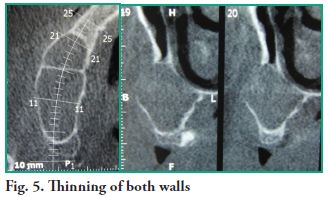

A computerized tomography (CT) scan is indicated for diagnostic purposes and to design a treatment plan. Images were obtained using single cone-beam x-ray CT and corroborated that the lesion measured 40.2 mm in the anterior-posterior direction by 30.1 mm in the vertical direction. All tomographic slices show that the right maxillary sinus is occupied by a lesion with septation near tooth 13, which has not deformed the nasal wall of the maxillary sinus (Figs. 4 and 5).

Clinically, the maxillary sinus mucocele can present swelling in the cheek, diplopia and teeth problems, although typically, without pain (3). In the early phases, diagnosis is fortuitous, taking place almost exclusively when a CT of the paranasal sinuses is taken (12). The cone beam computed tomography (CBCT) shows mucoceles as homogeneous, hypodense and isodense masses, as seen in a brain CT (13), and typically shows a rounded contour of bone (13-16), which makes the injection of a contrast medium unnecessary for diagnosis. This bone detail is an added advantage of the CBCT (15-17), since a radiopaque maxillary sinus, without bone erosion, would suggest a diagnosis of sinusitis, polyps and antral retention cysts (18). The typical maxillary sinus mucocele completely opacifies the antrum and expands the sinus cavity (10). During the early stages, it is not possible to differentiate a mucus-filled sinus with a temporary obstruction from a similar obstructed sinus, which will later form a mucocele. The definitive diagnosis can only be reached when there is sinus expansion (12, 19). If there is expansion and destruction of the bone, the differential diagnosis includes malignant conditions, such as adenoid cystic carcinoma, plasmacytoma, rhabdomyosarcoma, lymphoma, schwannoma and odontogenic tumors (14). Traditionally, bone erosion is not associated with maxillary sinus mucocele. In our patient it had thinned both the posterior and medial walls of the maxillary antrum, as described in the reference literature (4), with bone loss near tooth 16. We argue that a large mucocele can cause bone erosion, but the homogeneous nature of the maxillary lesion, together with the preservation of the layers of mucosa adjacent to the eroded bone, reveal the benign nature of the lesion. Histologically, the maxillary sinus mucocele is confined by an epithelial connective capsule made up of normal respiratory mucosa (pseudostratified ciliated cylindrical epithelium), with an underlying chorion that has fibrosis and chronic inflammation. Finding metaplastic squamous epithelium is rare, since the most common lining is ciliated respiratory mucosa (19-21). Many theories have been suggested to explain the mechanisms responsible for the formation and growth of mucoceles, including cystic degeneration of a seromucous gland, even though the histopathological and molecular examinations conducted by Lund et al. (22, 23) study a dynamic process of bone resorption, where inflammation takes part, through cytokines, which act between the bone and the epithelium releasing prostaglandins. These play a key role in the development of a mucocele, along with the sinus obstruction. Mucoceles, in turn, can be caused by a facial trauma or previous surgery which could result in compartmentalized areas such as the one our patient showed (8). Since the diagnosis in this case was uncertain, an incisional biopsy was initially planned, and when the procedure was performed and it was established that the lesion was clinically benign, it was completely removed. No nasal counter opening was made in the inferior meatus as indicated for this kind of procedure, therefore, nasal drops were prescribed to keep the ostium patent. To complement the surgical procedure, the patient was prescribed a dose of 500 mg of Amoxicillin every 8 hours for a period of no less than 7 days and a dose of 400 mg of Ibuprofen every 6 hours for a minimum of 48 hours, as an analgesic agent. The patient progressed favorably in the short term, in the two-month follow-up.

A computerized tomography (CT) scan is indicated for diagnostic purposes and to design a treatment plan. Images were obtained using single cone-beam x-ray CT and corroborated that the lesion measured 40.2 mm in the anterior-posterior direction by 30.1 mm in the vertical direction. All tomographic slices show that the right maxillary sinus is occupied by a lesion with septation near tooth 13, which has not deformed the nasal wall of the maxillary sinus (Figs. 4 and 5).

Clinically, the maxillary sinus mucocele can present swelling in the cheek, diplopia and teeth problems, although typically, without pain (3). In the early phases, diagnosis is fortuitous, taking place almost exclusively when a CT of the paranasal sinuses is taken (12). The cone beam computed tomography (CBCT) shows mucoceles as homogeneous, hypodense and isodense masses, as seen in a brain CT (13), and typically shows a rounded contour of bone (13-16), which makes the injection of a contrast medium unnecessary for diagnosis. This bone detail is an added advantage of the CBCT (15-17), since a radiopaque maxillary sinus, without bone erosion, would suggest a diagnosis of sinusitis, polyps and antral retention cysts (18). The typical maxillary sinus mucocele completely opacifies the antrum and expands the sinus cavity (10). During the early stages, it is not possible to differentiate a mucus-filled sinus with a temporary obstruction from a similar obstructed sinus, which will later form a mucocele. The definitive diagnosis can only be reached when there is sinus expansion (12, 19). If there is expansion and destruction of the bone, the differential diagnosis includes malignant conditions, such as adenoid cystic carcinoma, plasmacytoma, rhabdomyosarcoma, lymphoma, schwannoma and odontogenic tumors (14). Traditionally, bone erosion is not associated with maxillary sinus mucocele. In our patient it had thinned both the posterior and medial walls of the maxillary antrum, as described in the reference literature (4), with bone loss near tooth 16. We argue that a large mucocele can cause bone erosion, but the homogeneous nature of the maxillary lesion, together with the preservation of the layers of mucosa adjacent to the eroded bone, reveal the benign nature of the lesion. Histologically, the maxillary sinus mucocele is confined by an epithelial connective capsule made up of normal respiratory mucosa (pseudostratified ciliated cylindrical epithelium), with an underlying chorion that has fibrosis and chronic inflammation. Finding metaplastic squamous epithelium is rare, since the most common lining is ciliated respiratory mucosa (19-21). Many theories have been suggested to explain the mechanisms responsible for the formation and growth of mucoceles, including cystic degeneration of a seromucous gland, even though the histopathological and molecular examinations conducted by Lund et al. (22, 23) study a dynamic process of bone resorption, where inflammation takes part, through cytokines, which act between the bone and the epithelium releasing prostaglandins. These play a key role in the development of a mucocele, along with the sinus obstruction. Mucoceles, in turn, can be caused by a facial trauma or previous surgery which could result in compartmentalized areas such as the one our patient showed (8). Since the diagnosis in this case was uncertain, an incisional biopsy was initially planned, and when the procedure was performed and it was established that the lesion was clinically benign, it was completely removed. No nasal counter opening was made in the inferior meatus as indicated for this kind of procedure, therefore, nasal drops were prescribed to keep the ostium patent. To complement the surgical procedure, the patient was prescribed a dose of 500 mg of Amoxicillin every 8 hours for a period of no less than 7 days and a dose of 400 mg of Ibuprofen every 6 hours for a minimum of 48 hours, as an analgesic agent. The patient progressed favorably in the short term, in the two-month follow-up.